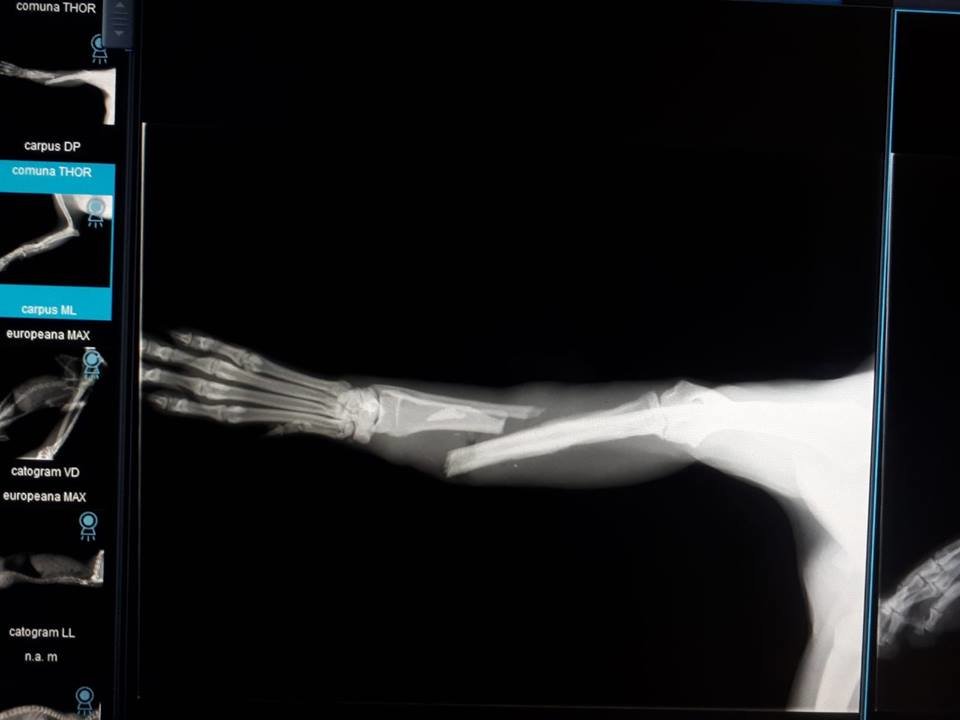

Meet Cleo. She was found in a ditch on the side of the road having been hit by a car. She had 3 broken bones in 2 legs. Her rescuer, Ani, could not afford to pay a vet for the massive veterinary costs that were being quoted by local vets, so Ani asked for our help. We welcomed Cleo into our Homeless Animals Hospital program.

Cleo needed her severly damaged leg to be amputated. She is learning to walk on three legs now. She is recovering at Family Vet in Craiova, and remarkably our Suzy has found her a great home in the UK!